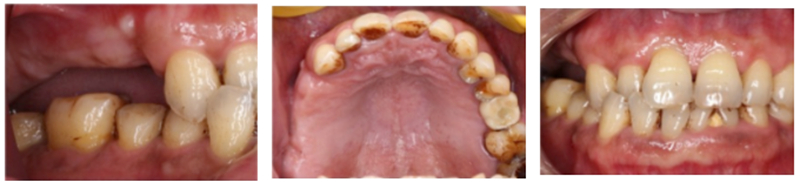

主訴:右側后牙缺失6個月以上,要求種植修復。

現(xiàn)病史: 多顆后牙連續(xù)缺失,未進行活動修復 。

檢查:患者14、15、16、17缺失,無紅腫潰瘍,牙齦情況良好,口腔衛(wèi)生狀況良好。

術前準備

®石膏模型上進行排牙確定患者咬合關系,取放射阻射材料灌于缺牙區(qū),患者戴著處理過的

配準裝置拍攝術前CBCT。

®根據(jù)CBCT中牙冠顯影位置,按照修復引導種植的原則進行方案設計